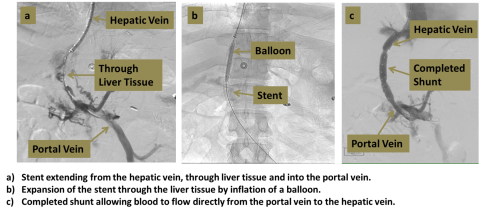

An interventional radiologist uses ultrasound and X-rays to guide a catheter into the vein draining the liver. A specialized needle is then passed through the inside of the liver and into the portal vein. A covered stent is placed to create a shunt from the portal vein to the hepatic vein, bypassing the liver and relieving the elevated portal vein pressure.